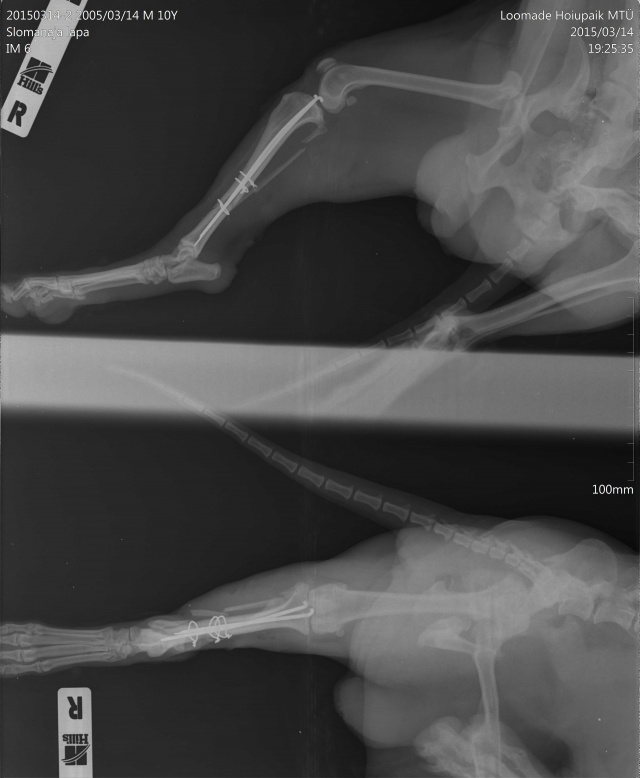

Tagumise käpa luumurd.

Koerake sattus varjupaika vigastatud käpaga. Ülevaatusel selgus, et koera käpal on mitmekordne luumurd. Pidime paigaldama ka kateetri, kuna ta ei saanud pissida (ilmselt autolöögist põhjustatud kusepõie atoonia).

Собака поступила в приют с множественным переломом ноги. Не могла пописать (видимо был удар машины и, как результат, атония мочевого пузыря). Нога в очень тяжёлом состоянии, и завтра мы кладём собаку на операционный стол.